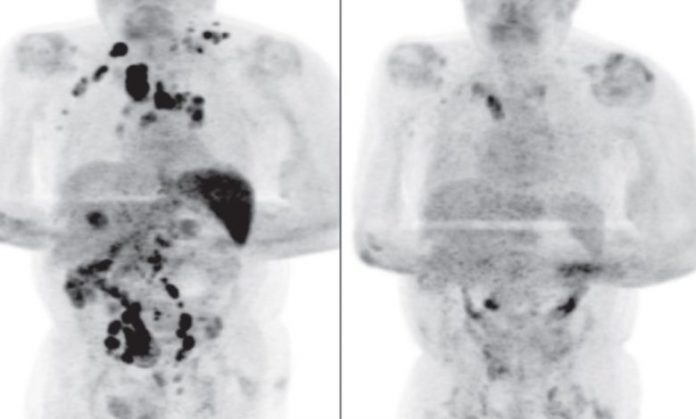

Durante la pandemia del COVID-19 se han presentado múltiples casos que han sorprendido a doctores y expertos; sin embargo, el de un hombre de 61 años dejó atónitos a todos al curarse de cáncer tras contagiarse del virus del SARS-CoV-2.

El caso del hombre que resultó contagiado de coronavirus y tiempo después su linfoma de Hodgkin, que había sido diagnosticado semanas antes, desapareció por completo, fue informado por dos médicos especialistas del departamento de Hematología del Hospital Royal Cornwall en el Reino Unido.

El misterioso caso fue presentado por los doctores Sarah Challenor y David Tucker en la revista British Journal of Haemathology, quienes explicaron que el hombre de 61 años había sido diagnosticado con cáncer por linfoma de Hodgkin en etapa 3, esto quiere decir que la enfermedad ya estaba en todo su cuerpo.

Además, arribó a la clínica con síntomas de adelgazamiento progresivo, masas palpables en diferentes partes de su cuerpo y también presentaba problemas renales que eran tratados con diálisis.

Sin embargo, tras su diagnóstico, el paciente volvió a la institución médica, aunque en esta ocasión presentaba problemas respiratorios a consecuencia del COVID-19, por lo que se mantuvo bajo cuidados médicos especiales durante 11 días.

Tras ser dado de alta, el hombre no volvió a la clínica hasta cuatro meses después a una consulta médica de rutina, ese día los doctores se llevaron una enorme sorpresa, pues el paciente mostró una notable mejoría ya que los ganglios ya no estaban inflamados.

Los especialistas consideraron que la “infección por SARS-CoV-2 desencadenó una respuesta inmunitaria antitumoral, como se ha descrito con otras infecciones en el contexto de linfoma no Hodgkin de alto grado”.

“Las citocinas inflamatorias producidas en respuesta a la infección podrían haber activado células T específicas con antígenos tumorales y células asesinas naturales contra el tumor”, mencionaron los médicos del departamento de Hematología del Hospital Royal Cornwall.